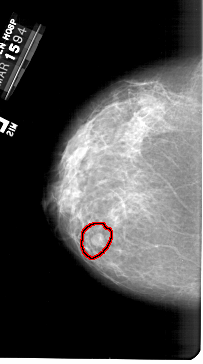

A_1387_1.LEFT_MLO

FILE: A_1387_1.LEFT_MLO.OVERLAY

TOTAL_ABNORMALITIES 1

ABNORMALITY 1

LESION_TYPE MASS SHAPE ROUND MARGINS CIRCUMSCRIBED

ASSESSMENT 4

SUBTLETY 4

PATHOLOGY BENIGN

TOTAL_OUTLINES 1

BOUNDARY